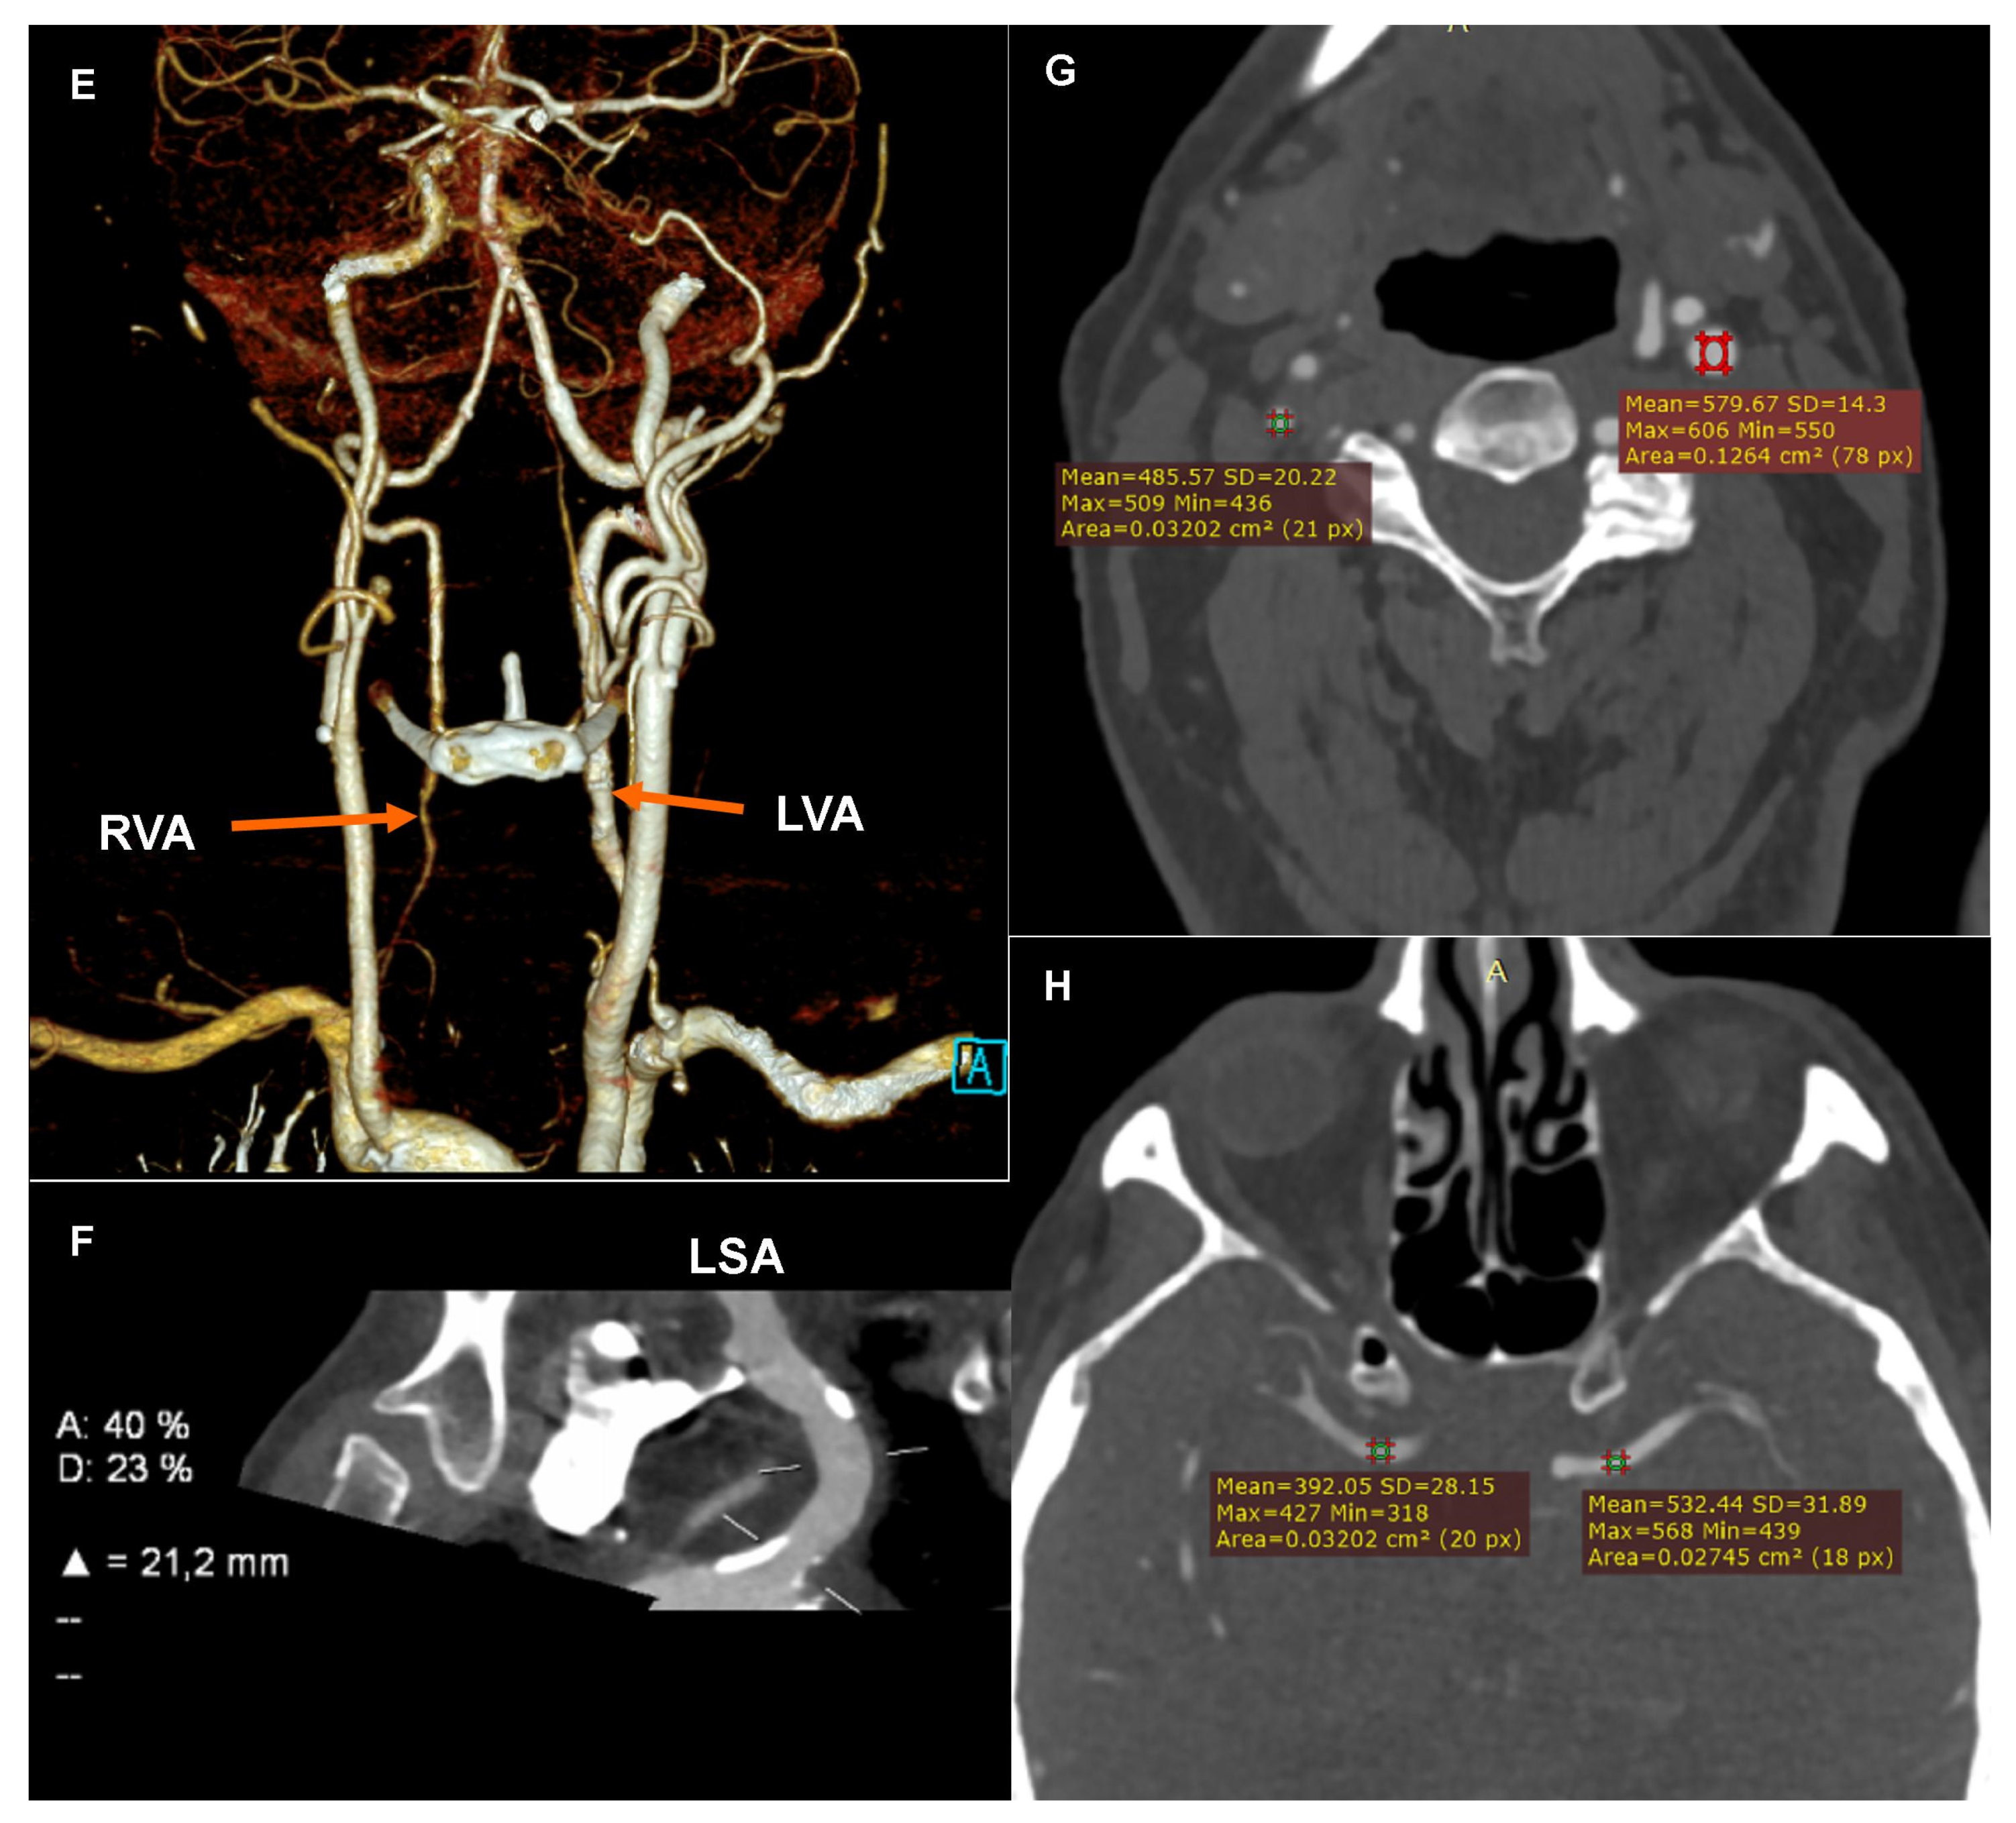

The CTA of the coronary arteries, performed using a 384-slice Siemens Force CT, revealed a coronary artery calcium score of 412.5 (left main (LM): 185, left anterior descending (LAD): 16.7, and left circumflex (LCx): 210.8), the value of which indicated a high risk of a significant coronary artery disease (Figure 1A); the examination revealed numerous atherosclerotic plaques of various morphotic types in the coronary arteries, causing short-segment stenosis, up to 50–70% within the left circumflex, right behind the origin of the 1. marginal branch (Figure 1B) and the long muscular bridge within the middle section of the left anterior descending, about 5.8 cm long (Figure 1C). The CTA images of the coronary arteries corresponded to level three in the CAD-RADS classification, meaning a moderate coronary disease with the presence of moderate LCx stenosis requiring an objective evaluation, optimally via functional tests [1].

Figure 1.

Computed tomography angiography (CTA): (A) Coronary CTA. Native phase. Axial reconstruction. Coronary artery calcium score measurement. The colors indicate the calcifications assigned to specific coronary arteries. (B) Coronary CTA. Angiographic phase. Curved multiplanar reconstruction (cMPR). Left circumflex (LCx). Measurement of the degree of stenosis. (C) Coronary CTA. Angiographic phase. Curved multiplanar reconstruction (cMPR). Left anterior descending (LAD). Measurement of the length of the myocardial muscle bridge. (D) Carotid CTA. Angiographic phase. Curved multiplanar reconstruction (cMPR). Brachiocephalic trunk (BCT). Measurement of the degree of ostial stenosis. The letter A indicates the level of vessel lumen measurement at the reference level, the letter B indicates the level of vessel lumen measurement at the level of maximum stenosis. Computed tomography angiography (CTA): (E) Carotid CTA. Angiographic phase. Volume rendering technique reconstruction (VRT). Arrows mark the recessive right vertebral artery (RVA) and the dominant left vertebral artery (LVA). (F) Carotid CTA. Angiographic phase. Curved multiplanar reconstruction (cMPR). Left subclavian artery (LSA). Measurement of the degree of stenosis. (G) Carotid CTA. Angiographic phase. Axial reconstruction. Measurement of the density of the proximal sections of the internal carotid arteries. Lower density of contrasted blood in the right carotid arteries. (H) Carotid CTA. Angiographic phase. Axial reconstruction. Measurement of the density of the cerebral arteries. Lower density of contrasted blood in the right cerebral arteries.